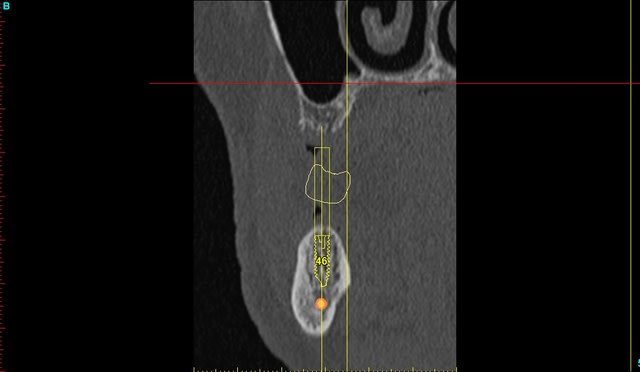

dommage j'ai oublié de prendre mes radios d'un ptit cas clinique fait vendredi...12/22 agénésies et il fallait vraiment viser juste pour éviter les racines des dents adjacentes...et être pile pour pouvoir faire les couronnes provisoires transvissées...

je ne devais pas avoir plus d'un demi mm et 1° de marge d'erreur possible pour ces 2 implants...

j'aurais quasi pu faire l'intervention les yeux fermés (enfin quand même pas car il me fallait quand même contrôler ma cible sur la machine...)

je posterai les images du scan et les radios post op du cas dont je viens de parler mardi ou mercredi, c'est quand même intéressant de voir ce que l'on arrive à faire avec et avoir comme précision...je n'ai presque pas décollé (petites incisions crestales en W pour aménager les futures papilles), posé les implants et réalisé les 2 couronnes prov transvissées en une petite heure seulement...

sincèrement, sans, j'aurais ouvert en très grand pour contrôler la position exacte des racines et fait un litre d'huile avec une seule olive entre les fesses lors du forage...tout en mitraillant avec des radios à chaque mm de progression...de peur de toucher aux dents adjacentes...

mais là, même pas une petite goutte de sueur...

je mets les coupes et les radios post op...

intervention "quasi" flaless, juste des incisions crestales en W pour manager les papilles...